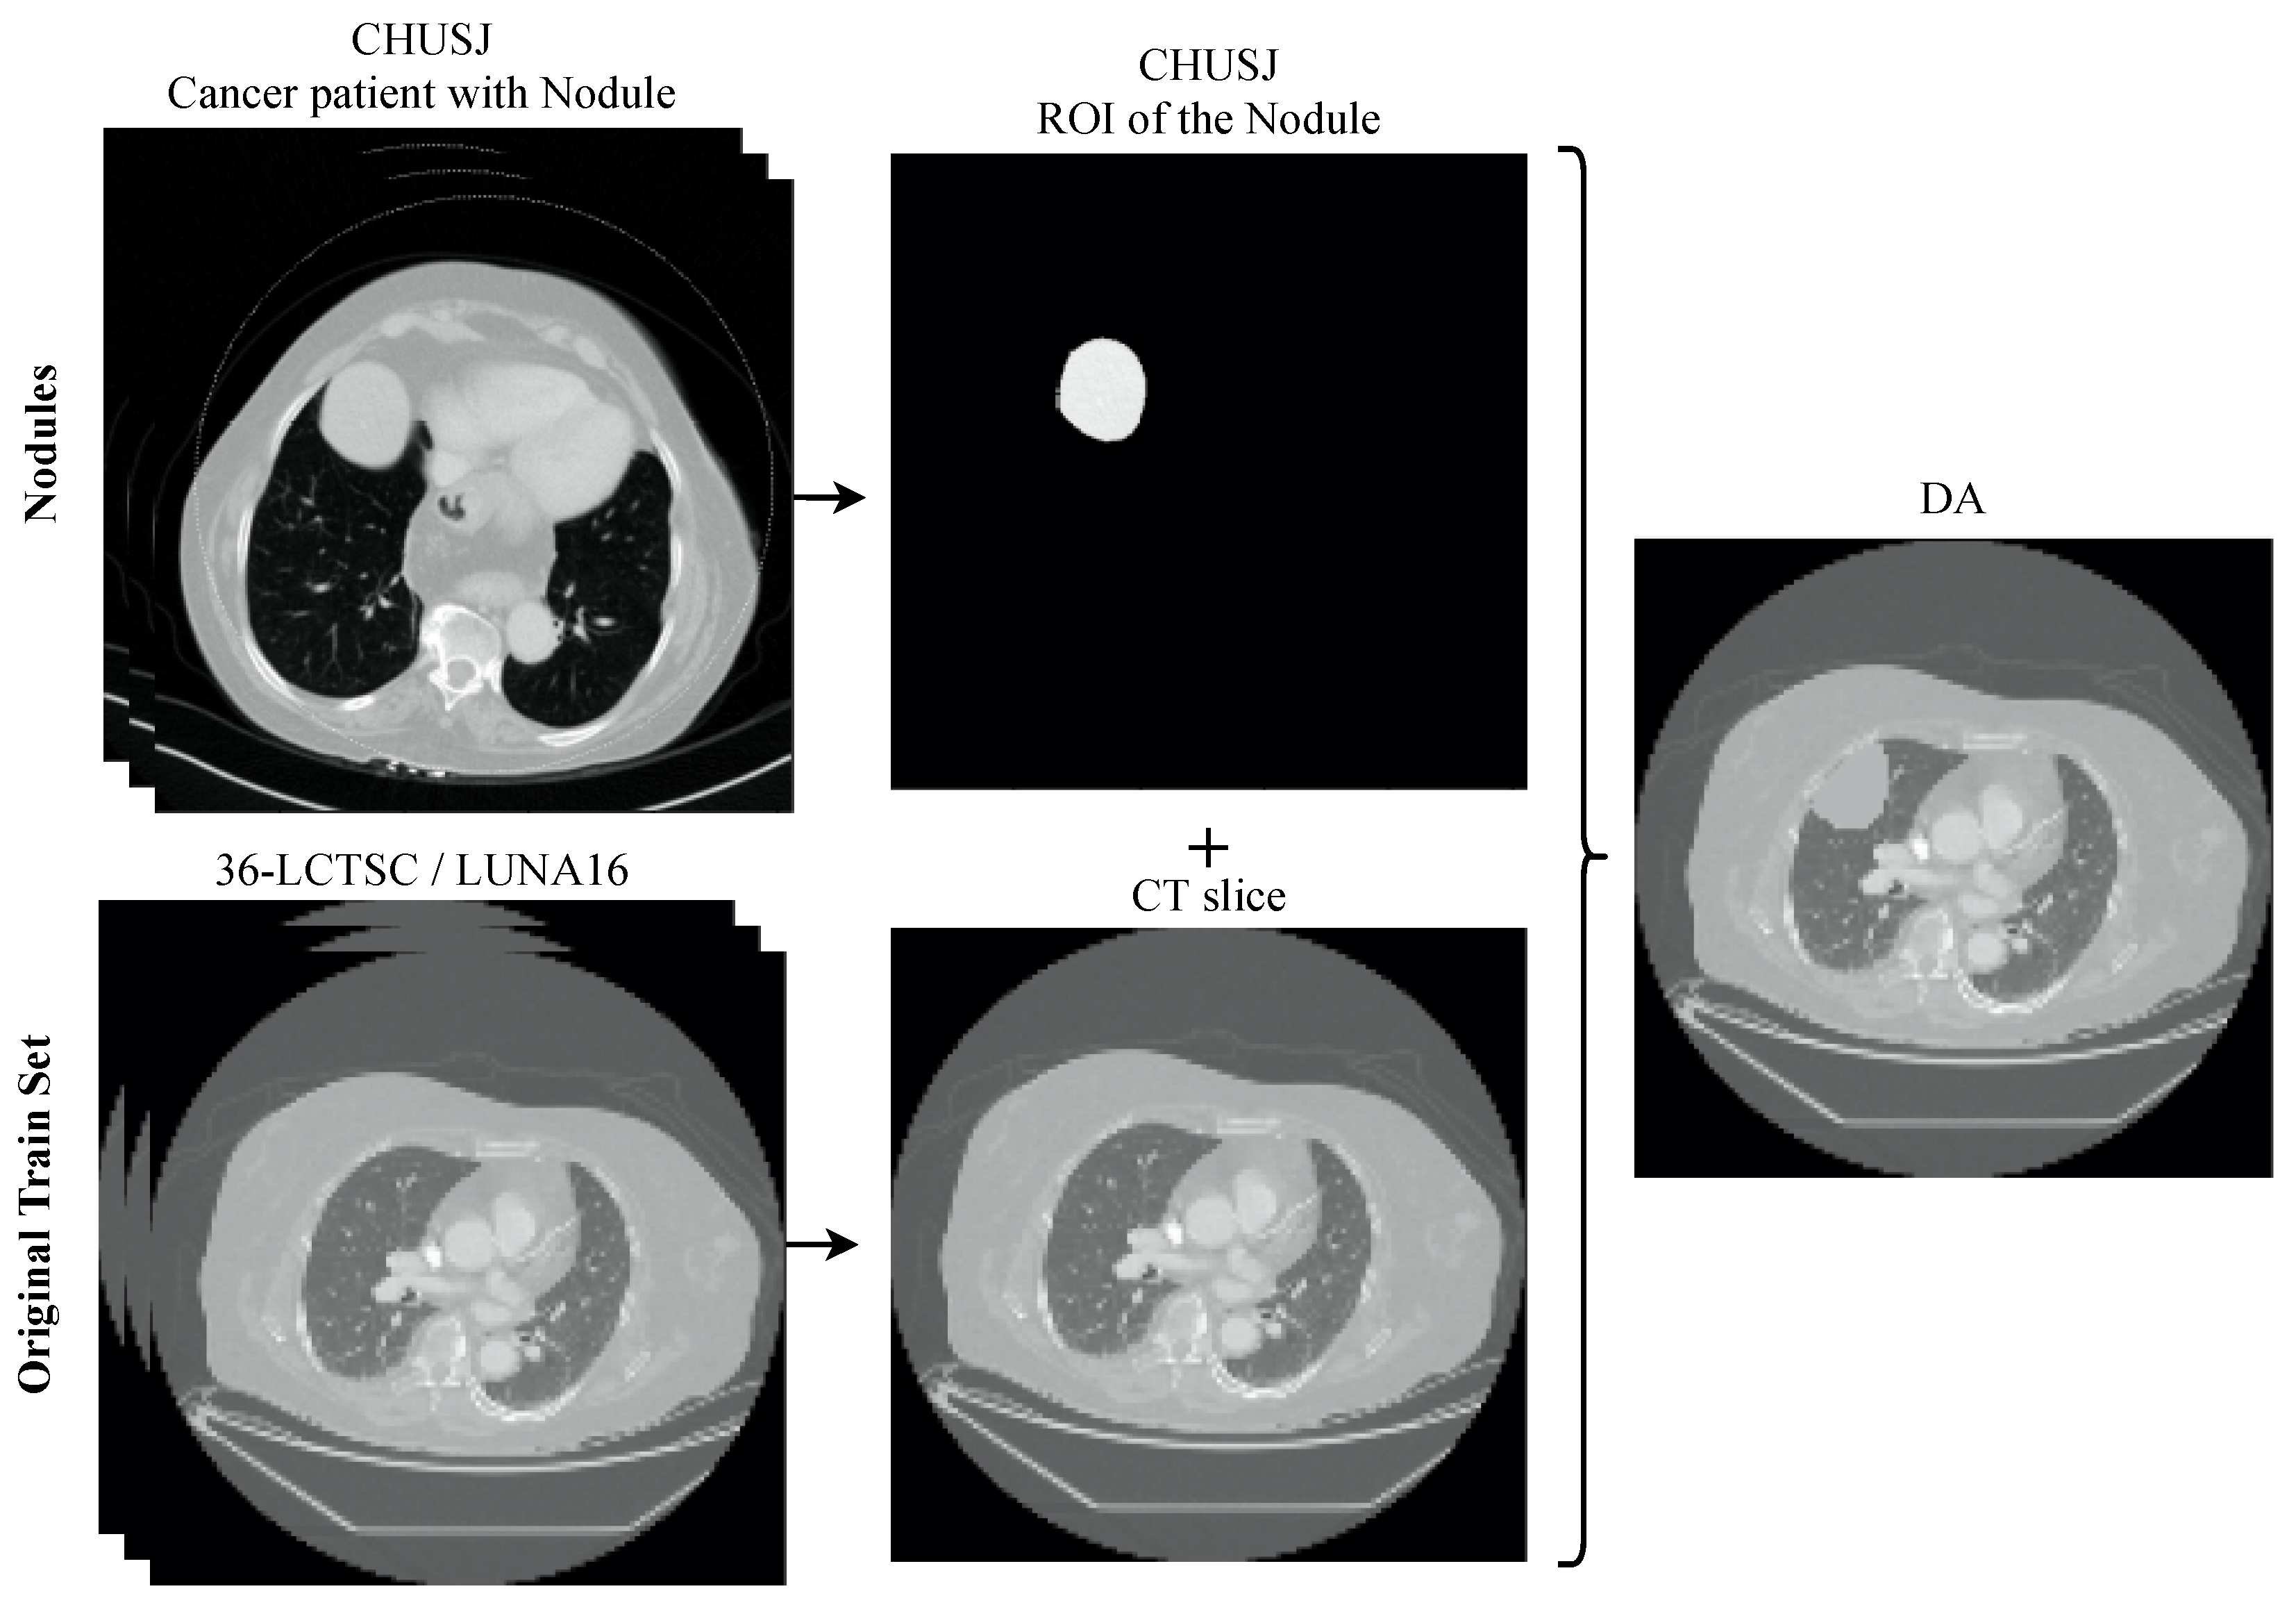

2.5. Data Augmentation